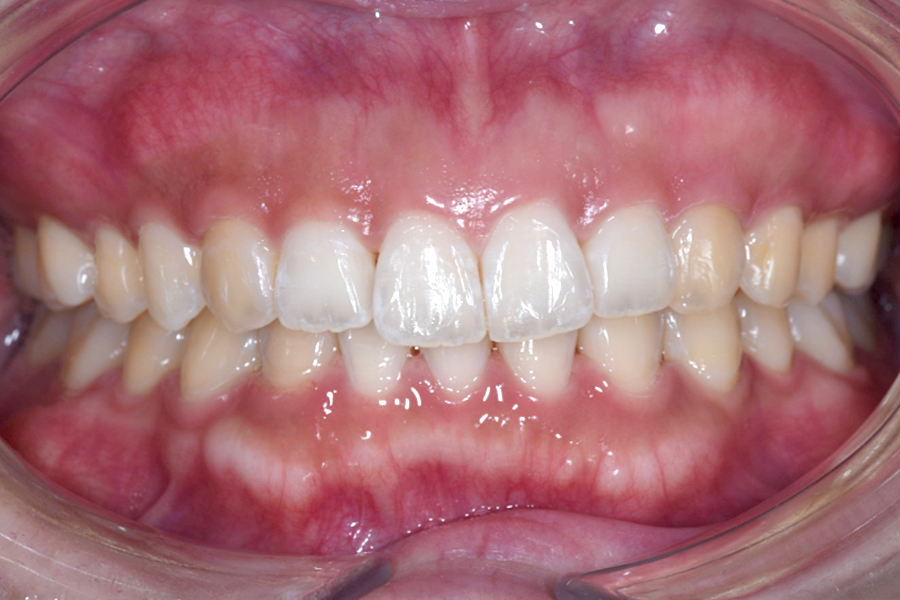

| 主訴 | 見た目を治したい、歯を白くしたい |

|---|---|

| 治療期間 | 1年6か月 |

| 治療費 | マウスピース矯正と ホームホワイトニングセット 1,022,350円(税込) |

| 治療内容 | 目立ちにくいマウスピース矯正 (非抜歯矯正) 歯と歯の間に隙間をつくることにより、歯列弓を広げながら治療を行いました。 また矯正用マウスピースをトレー代わりにし、ジェルを入れてホームホワイトニングを同時に行っております。 |

| 治療のリスク | ・後戻りする可能性があるのでリテーナーを最低でも矯正期間以上はつける必要があります。 ・ホワイトニング後、一時的に痛みが出る場合があります。 |